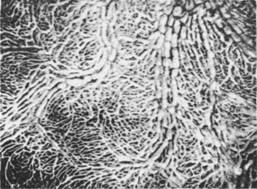

Рис. 1.3. Лимфатические сосуды диафрагмальной поверхности печени.

Кровоснабжение печени осуществляется ветвями собственной печеночной артерии. Кроме того, в печень поступает венозная кровь из воротной вены. Венозная кровь из паренхимы печени смешивается с кровью воротной вены и вместе с последней оттекает через печеночные вены и нижнюю полую вену. Лимфатических капилляров внутри долек печени нет, они сосредоточены в периваскулярной фиброзной капсуле как внутри, так и на поверхности органа (рис.1.3,1.4). Отводящие лимфатические сосуды следуют к печеночным, чревным, правым желудочным, диафрагмальным и задним медиастинальным лимфатическим узлам. Иннервация печени и желчных путей осуществляется ветвями печеночного сплетения (блуждающие и диафрагмальные нервы, симпатический ствол).